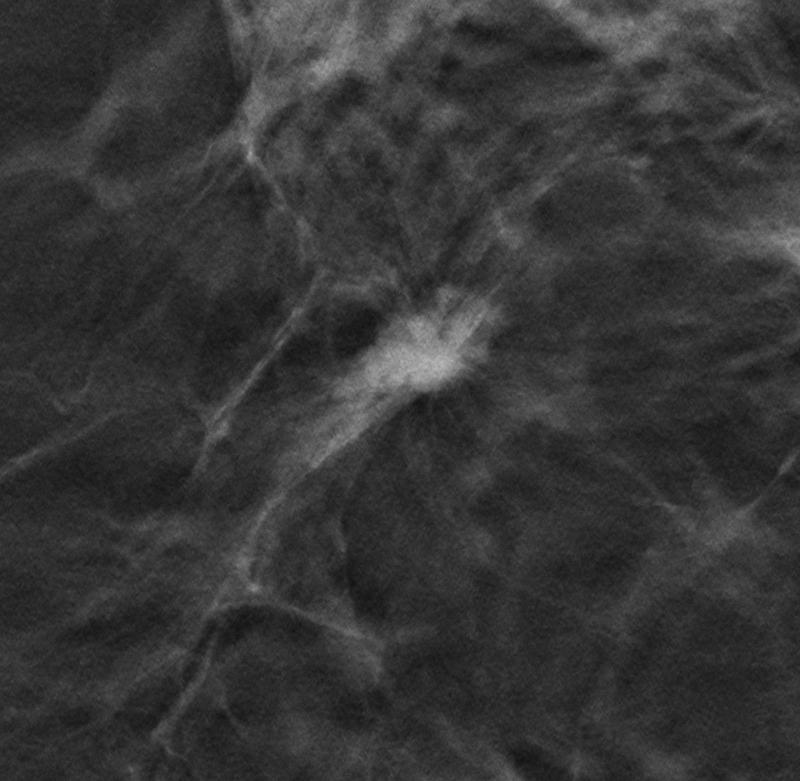

Bei den fast 100.000 Studienteilnehmerinnen von TOSYMA kam eine Kombination aus der DBT – kurz für Digitale Brust-Tomosynthese – und synthetischen 2D-Mammographen (SM) zum Einsatz. Die interdisziplinäre Studiengruppe unter der Leitung von Prof. Walter Heindel, Direktor der münsterschen Uniklinik für Radiologie, verglich die mit dem kombinierten – DBT+SM genannten – Verfahren gewonnenen Daten mit denen aus dem Screening mit der herkömmlichen Digitalen Mammographie (DM). Das Ergebnis: DBT+SM führt im Vergleich zum bislang gängigen Vorgehen mit DM zu einer signifikant höheren Entdeckung von Frauen mit invasivem Brustkrebs. Allerdings: Das muss nicht gleichbedeutend sein mit einer verbesserten Frauengesundheit – Stichwort Überdiagnostik. Mit anderen Worten: Dass DBT+SM Brustkrebs besser „findet“, ist erwiesen – nun galt es aber zu untersuchen, ob dies auch tatsächlich zu einer erwartbaren Verbesserung für die betroffenen Brustkrebs-Patientinnen führt.

In einer Subanalyse prüften Prof. Dr. Stefanie Weigel, Prof. Dr. Walter Heindel und Prof. Dr. Hans-Werner Hense, welche Tumore in einem früheren Brustkrebsstadium häufig entdeckt werden – und erkannten, dass mittels DBT+SM-Screening relevante Tumore entdeckt werden können, also jene, die – im Gegensatz zu wenig aggressiven Varianten – potenziell für eine Senkung der Sterblichkeit an Brustkrebs relevant sind. Stefanie Weigel resümiert: „Aus den Ergebnissen der Subanalyse folgern wir, dass die höhere Rate an frühen Tumorstadien der Tumorgrade 2 und 3 durch den Einsatz von DBT+SM den Screening-Effekt bezüglich der Brustkrebssterblichkeit erhöhen könnte“ – ein weiterer Pluspunkt für DBT+SM.